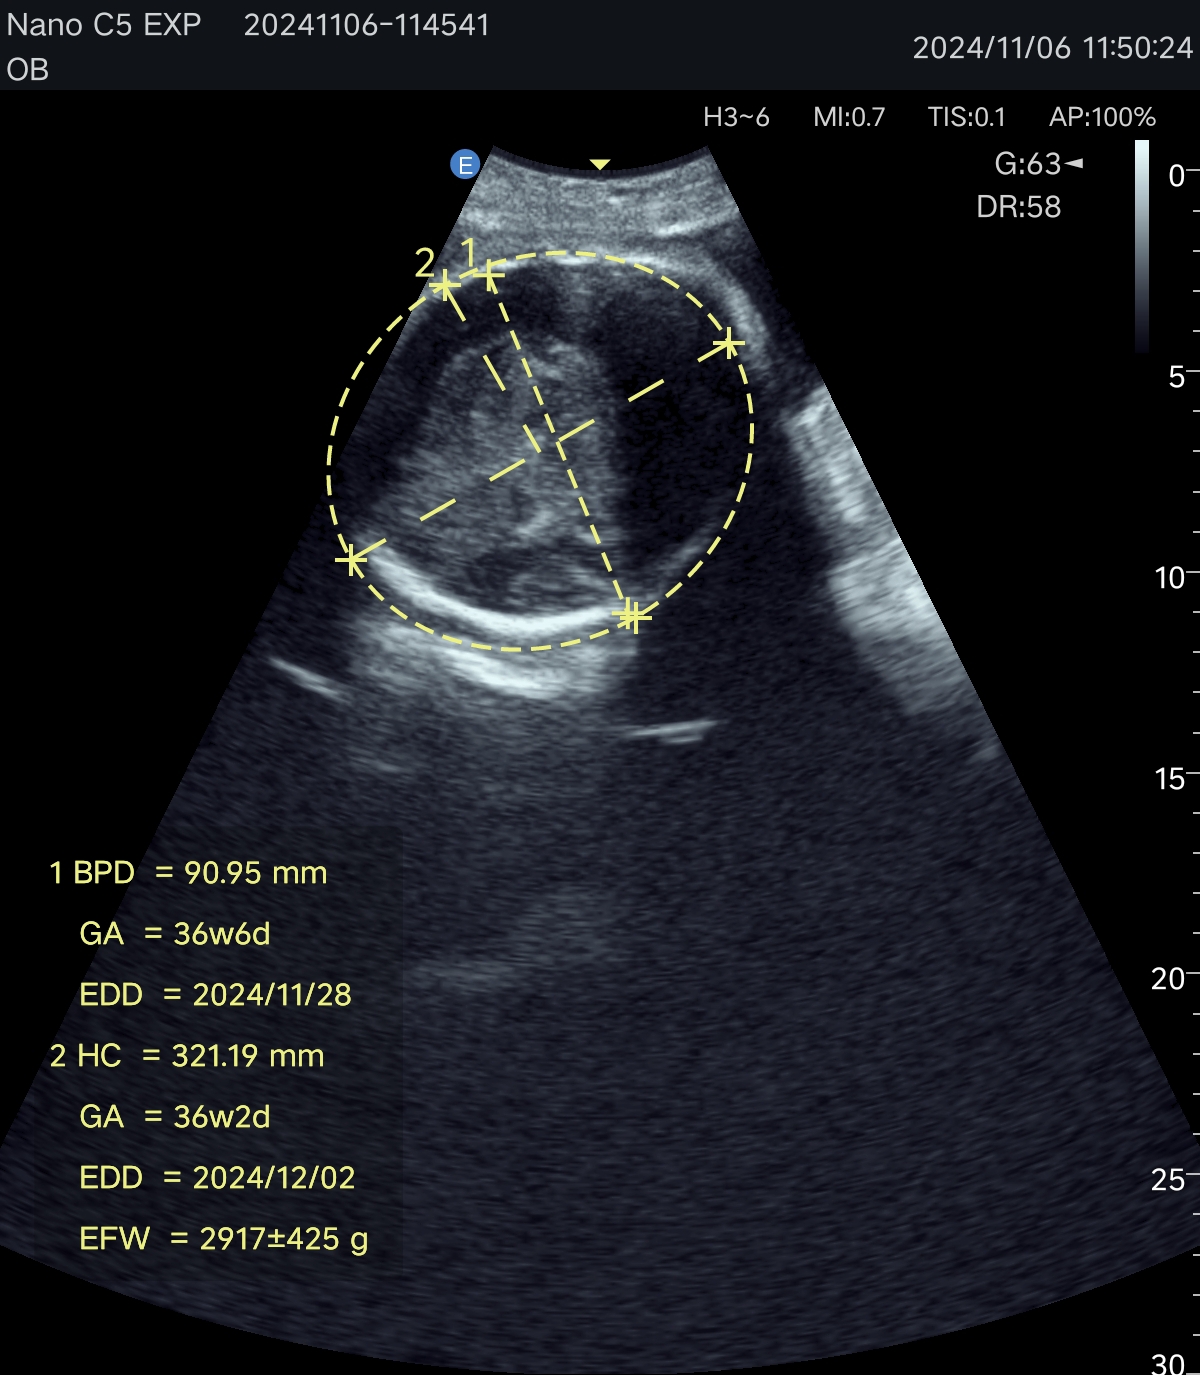

Портативная ультразвуковая система EDAN Nano, созданная на базе новейшей платформы для зональной сонографии SynSight, меняет представление о портативности и производительности в диагностике на месте оказания медицинской помощи. Это революционное устройство, обеспечивающее превосходное качество изображения в компактном корпусе, сочетает в себе передовые технологии и непревзойденную мобильность, что делает его незаменимым инструментом в динамичной клинической среде — от первичного осмотра пациентов в экстренных ситуациях и оказания помощи на месте до обследования пациентов в стационаре, ухода на дому и первичной медико-санитарной помощи.

Технология зональной сонографии — это совершенно новый подход к получению и обработке ультразвуковых изображений. EDAN SynSight может использовать всю информацию, содержащуюся в наборе эхо-данных, полученных в каждой большой зоне, и таким образом охватывать поле зрения за меньшее количество циклов передачи/приёма. Исходная необработанная эхо-информация многократно обрабатывается в процессоре канальной области для формирования оптимальных изображений.

Используйте перспективную технологию визуализации в портативном УЗ-сканере. Интерфейс устройства интуитивно понятен, а применение современных режимов сканирования обеспечивает эффективную и точную диагностику в различных клинических ситуациях. Аппарат оптимален как для работы в клинике, так и для неотложной помощи, повышая качество обследования у постели больного.